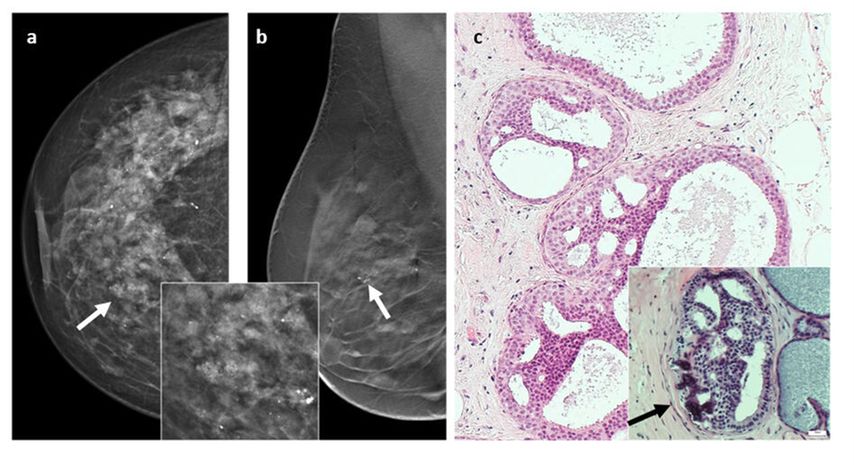

Die ADH ist eine niedriggradige klonale intraduktale Läsion von ≤2mm Durchmesser und häufig mit Mikroverkalkungen vergesellschaftet (Abb. 1). Sie zeigt histopathologische Ähnlichkeiten mit dem duktalen Carcinoma in situ (DCIS).3 In der klinischen Bildgebung, insbesondere in der Mammografie, sind die mit ADH vergesellschafteten Mikroverkalkungen häufig gut zu erkennen und daher stellt die ADH den grössten Anteil von B3-Läsionen, welche mittels Mammografie-gesteuerter VAB diagnostiziert werden.6 Die Upgrade-Rate für einen malignen Befund beträgt in der aktuellen Literatur 31–78% (nach Stanzbiopsie) und 19–41% (nach VAB).7 In den aktuellen englischen Guidelines wird eine Vakuum-assistierte Exzision (VAE) als Alternative zur offenen Operation empfohlen. Dabei sollten zumindest 4g als Resektionsgewebe mittels VAB entnommen werden, um höhergradige Läsionen auszuschliessen.8 Bei der Konsensuskonferenz empfahl die Mehrheit des Panels (76%) generell eine weitere Intervention nach Diagnose durch eine Stanzbiopsie, nach Diagnose durch VAB, sofern der Befund in der klinischen Bildgebung zu ≥90% entfernt wurde, eine offene Operation in 58%.

Abb. 1: Atypische duktale Hyperplasie (ADH). a) und b): Darstellung in der Mammografie mit Mikrokalk (Pfeile), c) histopathologisches Korrelat (H-&-E-Färbung). Abbildung aus Elfgen C et al.1